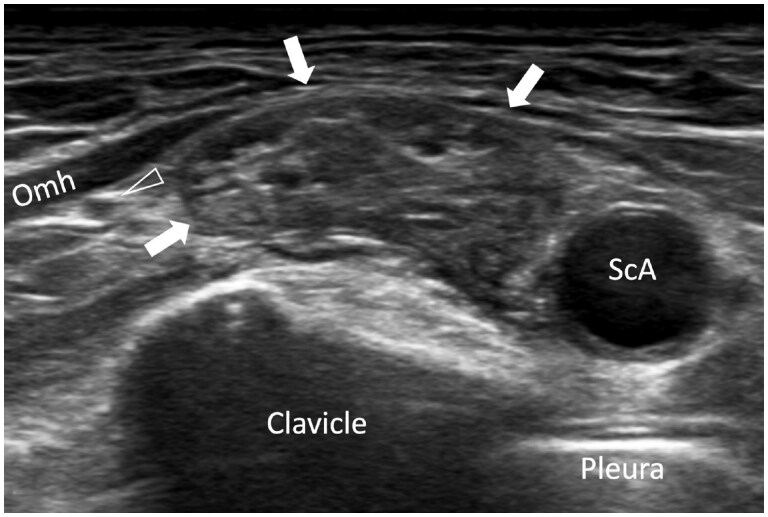

Ultrasound is as accurate as MRI in the detection of most brachial pathologies but tends to be underutilized in clinical practice compared to MRI. The main reason for this under-usage is a relative lack of knowledge regarding how to perform brachial plexus ultrasound and a lack of awareness of the ultrasound appearances of brachial pathologies. This review serves to re-address this imbalance by providing a practical overview on how to perform brachial plexus ultrasound as well as highlighting the ultrasound appearances of common pathologies likely to be encountered in everyday clinical practice.